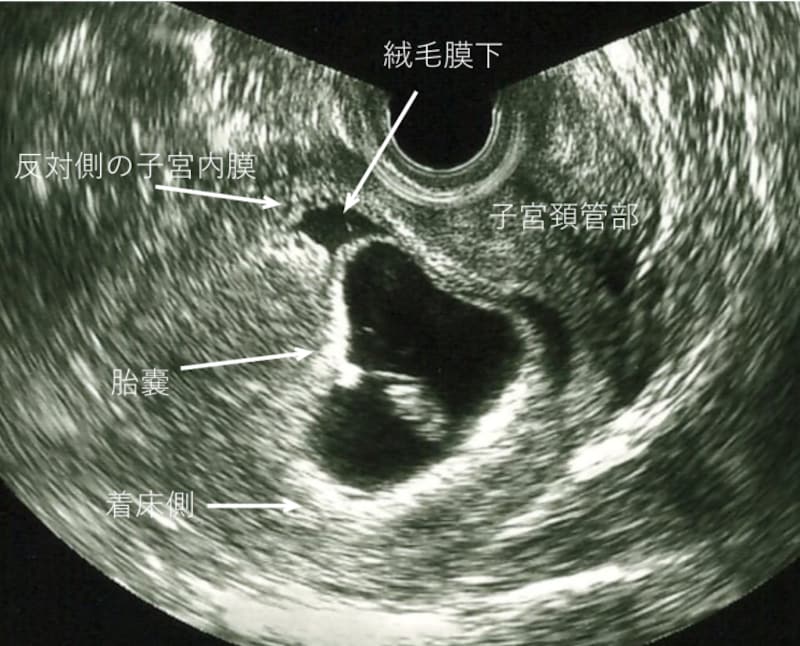

妊娠初期の出血4.絨毛膜下出血(血腫)

超音波検査で胎嚢が見え始めてから、胎嚢周囲に液体の貯留を認めることがあります。この場合、「子宮内に出血の痕がある」「子宮の壁と胎児の袋の間に血が溜まっている」などと説明があります。

偽月経の出血が、子宮内に残っている程度であれば、通常生活は問題ありませんが、胎児心拍が確認できる頃になっても、腟出血が続き、胎嚢の周囲で、新たな出血を繰り返している場合には、安静、休業の指示や、薬が処方されることもあります。